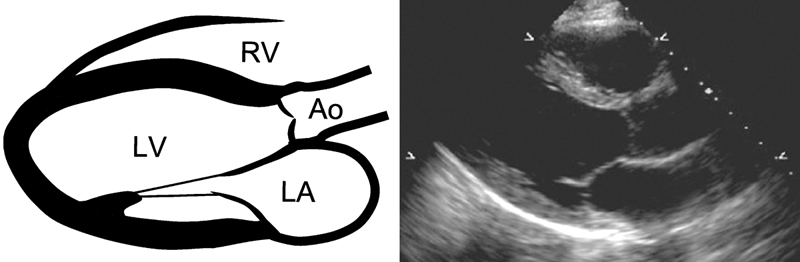

فحوصات تشخيصية لبعض امراض القلب والشرايين التاجية